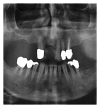

Infections are increasingly considered as potential trigger for carcinogenesis apart from risk factors like alcohol and tobacco. The discussion about human papilloma virus (HPV) in oral squamous cell carcinoma (OSCC) points at a general role of infection for the development of oral carcinomas. Furthermore, first studies describe a correlation between chronic periodontitis and OSCC, thus, characterizing chronic inflammation as being a possible trigger for OSCC. In front of this background, we present four well-documented clinical cases. All patients showed a significant anatomical relation between OSCC and clinical signs of chronic periodontitis. The interindividual differences of the clinical findings lead to different theoretical concepts: two with coincidental appearance of OSCC and chronic periodontitis and two with possible de novo development of OSCC triggered by chronic inflammation. We conclude that the activation of different inflammatory cascades by chronic periodontitis negatively affects mucosa and bone. Furthermore, the inflammatory response has the potential to activate carcinogenesis. Apart from a mere coincidental occurrence, two out of four patients give first clinical hints for a model wherein chronic periodontitis represents a potential risk factor for the development of OSCC.